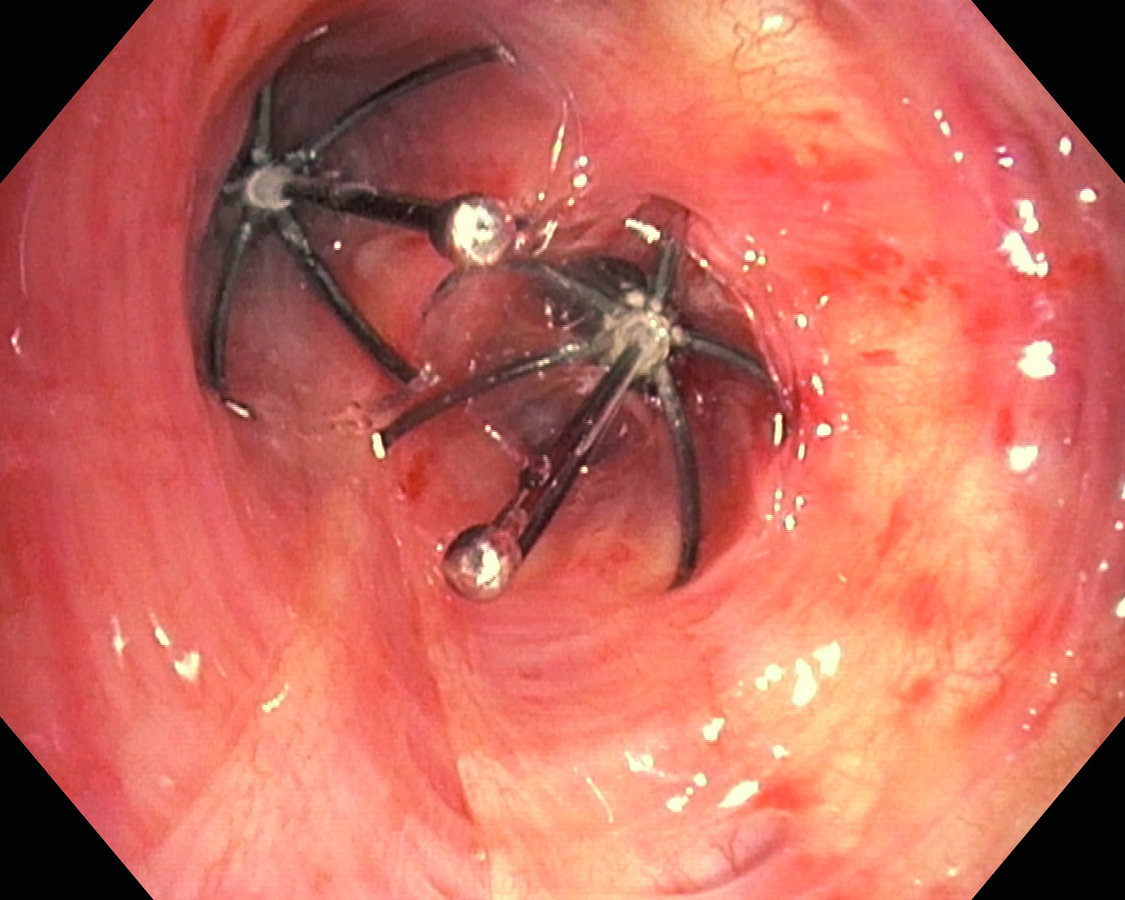

Eine häufig angewandte Methode zur endoskopischen Lungenvolumenreduktion (ELVR) ist die Implantation von blockierenden Einwegventilen. Sie werden in die Bronchien eingesetzt, die in den am meisten beschädigten und überblähten Lungenlappen führen. Die kleinen Ventile lassen bei der Ausatmung Luft und Sekrete entweichen, bei der Einatmung verhindern sie den Einstrom von Luft in die distalen Atemwege. Auf diese Weise kann sich der behandelte Lungenlappen allmählich entblähen, und das Volumen nimmt ab. Je größer die Volumenreduktion, desto besser für die Lungenfunktion und Belastbarkeit des Patienten. „Im Idealfall bildet sich eine vollständige Atelektase aus“, schreiben die Autoren. Heute wird bei der bronchoskopischen Ventiltherapie ein einzelner Lungenlappen komplett verschlossen, entweder ein Ober- oder ein Unterlappen.

Hier hat man mit einem intrabronchialen Ventil den linken Oberlappen verschlossen.